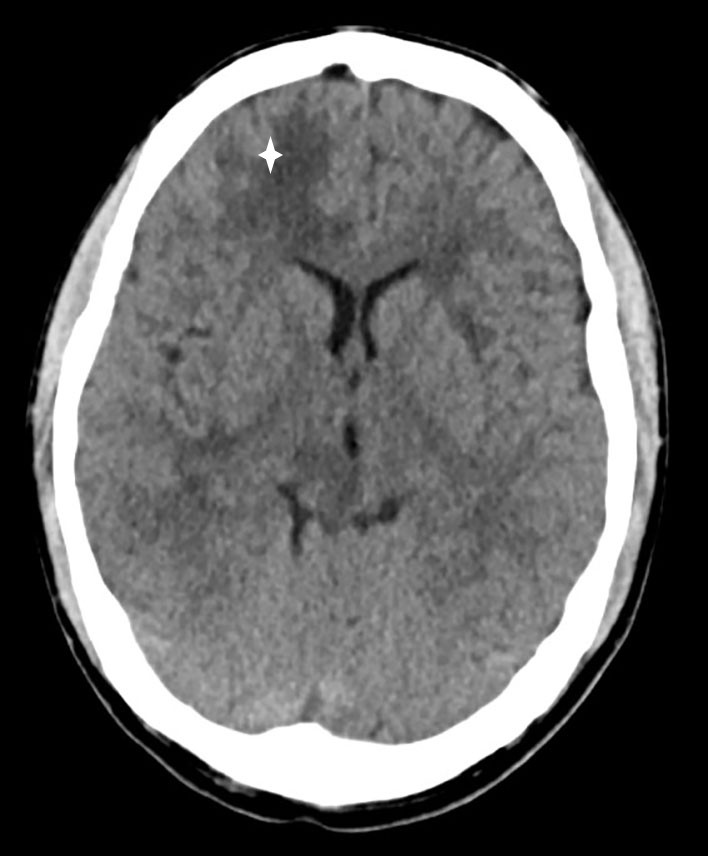

A CT scan of the head without contrast was taken immediately after admission and showed low-attenuation changes in frontal white matter in the right cerebral hemisphere (Fig. 1) and in the right cerebellar hemisphere. Supplementary magnetic resonance tomography of the brain and medulla the following day revealed multiple lesions in the brain stem, cerebellum and both cerebral hemispheres (Fig. 2). The neuroradiologist regarded the findings as consistent with multiple metastases, cerebral tuberculosis, a parasitic disease or septic emboli with secondary abscess formation. Cerebrospinal fluid analysis revealed a leukocyte level of 9 · 109/l, but otherwise normal values for erythrocytes, glucose and protein. The same evening, CT scans of the thorax, abdomen and pelvis were carried out to look for signs of extracerebral disease, including cancer, bacterial infection focus, tuberculosis in or outside the lungs, or signs of a parasitic disease. They revealed multiple micronodules in the lungs, most in the apical parts of both upper lobes, one slightly larger nodule in the apical lateral segment of in the left upper lobe and a small high-attenuation lesion to the right of the entry of the right main bronchus, consistent with a calcified lymph node (Fig. 3). There were multiple low-attenuation lesions in the abdomen and pelvis, most of them in the upper part of the liver, and in addition lesions in the kidneys and prostate. The radiologist described the findings as most consistent with miliary tuberculosis.

Figure 1 CT head without contrast medium showing low-attenuation changes in frontal white matter in the right cerebral…

Figure 1 CT head without contrast medium showing low-attenuation changes in frontal white matter in the right cerebral hemisphere (star).